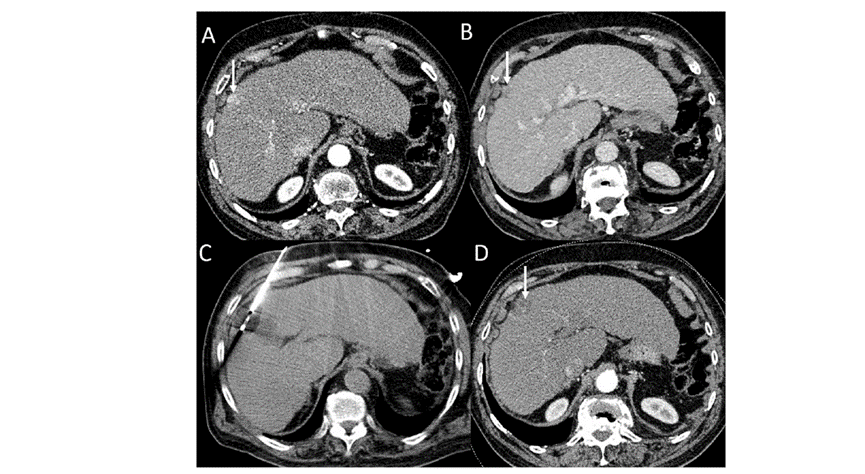

(A)動(dòng)脈期CT圖像顯示有一個(gè)包膜下結(jié)節(jié)(箭頭)。(B)門靜脈期CT圖像顯示病灶區(qū)(箭頭)。(C) 在手術(shù)過程中的CT顯示一個(gè)冷凍探針位于病灶內(nèi)。(D)消融后,術(shù)后1個(gè)月影像CT顯示完全消融。患者在手術(shù)及住院期間無并發(fā)癥及重大并發(fā)癥發(fā)生。隨訪時(shí)間中位數(shù)為7個(gè)月(范圍:3-12個(gè)月),隨訪期間患者無局部腫瘤進(jìn)展或死亡。

技術(shù)成功率為100%,本研究中77.8%(7/9)的患者達(dá)到了完全消融,輔助局部治療后,所有患者均完全消融。

膽囊附近轉(zhuǎn)移灶(來自子宮頸癌)的冷凍消融術(shù)(A)門靜脈期 CT 圖像顯示膽囊附近有病變(箭頭)。(C) 手術(shù)過程中CT 顯示冷凍探針位于病灶內(nèi)。(D)消融手術(shù)后 1 個(gè)月CT 顯示完全消融。

本研究中患者隨訪期間無局部腫瘤進(jìn)展,無死亡病例,沒有發(fā)現(xiàn)與手術(shù)相關(guān)的并發(fā)癥。證實(shí)冷凍消融是一種有效的治療方式,在技術(shù)上是可行和安全的。由于肝包膜下病變位置特殊,射頻消融有出血及腫瘤種植的風(fēng)險(xiǎn),可能會(huì)對(duì)鄰近器官造成損傷,并且增加局部腫瘤進(jìn)展的風(fēng)險(xiǎn)。近年來,冷凍消融術(shù)的應(yīng)用逐漸廣泛,有研究顯示冷凍消融治療具有明顯優(yōu)勢(shì),可治療特殊部位的肝腫瘤。本研究的目的是評(píng)價(jià)冷凍消融治療肝包膜下腫瘤的安全性和有效性。回顧性納入2016年7月1日至2018年9月1日期間冷凍消融的57例患者。包括42例男性和15例女性,平均年齡為62.4歲(范圍:48-82歲)。每個(gè)患者有1個(gè)或2個(gè)平均腫瘤尺寸為2.4cm的病變(范圍:0.6-4.0cm)。所有患者均患有慢性肝病或肝硬化,并伴有乙型肝炎(n=52)、丙型肝炎(n=3)和其他肝炎(n=2)。根據(jù)腫瘤位置,在膈肌或肝臟下附近有18個(gè)病變(26.5%),胃或腸附近有9個(gè)病變(13.2%),腹壁附近有33個(gè)病變(48.5%),腎臟附近有8個(gè)病變(11.8%)。